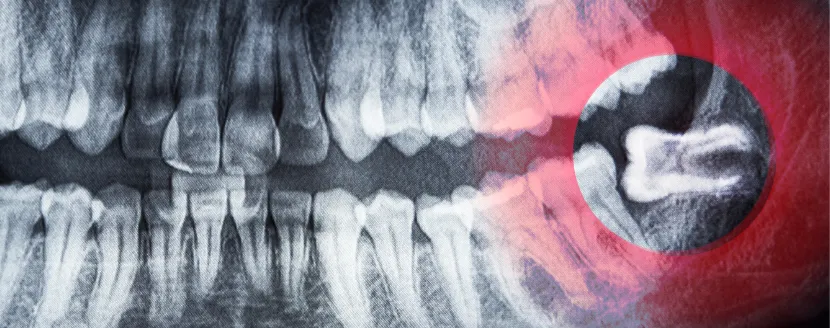

- Revisar todas las piezas dentales con radiografías y exploración clínica.

¿Es posible sacar muela del juicio con brackets puestos?

Sí, pero requiere una buena coordinación entre el ortodoncista y el cirujano dentista. Si la extracción no afecta directamente los dientes que llevan brackets, es perfectamente viable realizarla en medio del tratamiento.

En algunos casos, se pueden retirar temporalmente los brackets de la zona para facilitar la cirugía y recolocarlos después.